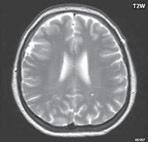

Obr. I.1.8a Dandy-Walkerova malformace, rozšířená IV komora (tvar klíčové dírky)

Obr. I.1.8b Dandy-Walkerova malformace, rozšířená IV komora široce komunikující s cisterna magna, hypotrofie mozečku (snímky zapůjčeny z archivu prim doc MUDr M Mechla, Ph D, MBA)

Obr. I.1.8c Dandy-Walkerova malformace, rozšířená IV komora široce komunikující s cisterna magna, hypotrofie mozečku (snímky zapůjčeny z archivu prim doc MUDr M Mechla, Ph D, MBA); stejný pacient jako na obr I 1 8b

Obr. I.1.8d Dandy-Walkerova malformace, rozšířená IV komora široce komunikující s cisterna magna, hypotrofie mozečku, vysoký úpon tentoria (šipka) (snímky zapůjčeny z archivu prim doc MUDr M Mechla, Ph D, MBA); stejný pacient jako na obr I 1 8b, c

V současné odborné literatuře je nejčastěji užíván termín D-W spektrum, který snad nejlépe vyjadřuje velmi široké možnosti vrozených změn zadní jámy lební. Mezi tuto skupinu cystických malformací zadní jámy lební pak řadíme klasickou malformaci D-W a její varianty, mega cisterna magna, arachnoidální cystu zadní jámy lební a retrocerebelární vak (Blake’s pouch cysta). Zařazení malformace do určité klinické jednotky není někdy jednoznačné, proto je možná výhodnější a přesnější vycházet z přesného popisu zobrazených změn. Příčina D-W malformace není známa, nabízejí se dvě hypotézy: 1. nepropustná spodina IV. komory, eventuálně uzávěr nebo pozdní otevření otvorů, kterými proudí likvor ze IV. komory. 2. primární hypogeneze mozečku. Embryonální vývoj mozečku ze všech hlavních struktur mozku trvá nejdelší dobu, a proto je velmi vulnerabilní k různým patologickým příčinám po dlouhou dobu svého vývoje.

Zobrazení

D-W malformace je charakterizována hypoplazií vermis mozečku, rozšířením IV. mozkové komory, která se často cysticky vyklenuje dorzálně a může imitovat arachnoidální cystu, rozšířením zadní jámy lební a vysokým úponem tentoria s confluens sinum nad lambdovým švem. Okcipitální kost může být vlivem tlakových změn remodelována, existují i případy s porušením její kontinuity a encefalokélou. Hydrocefalus pozorujeme v 80 %, častá je přítomnost dysgeneze corpus callosum, schizencefalie.